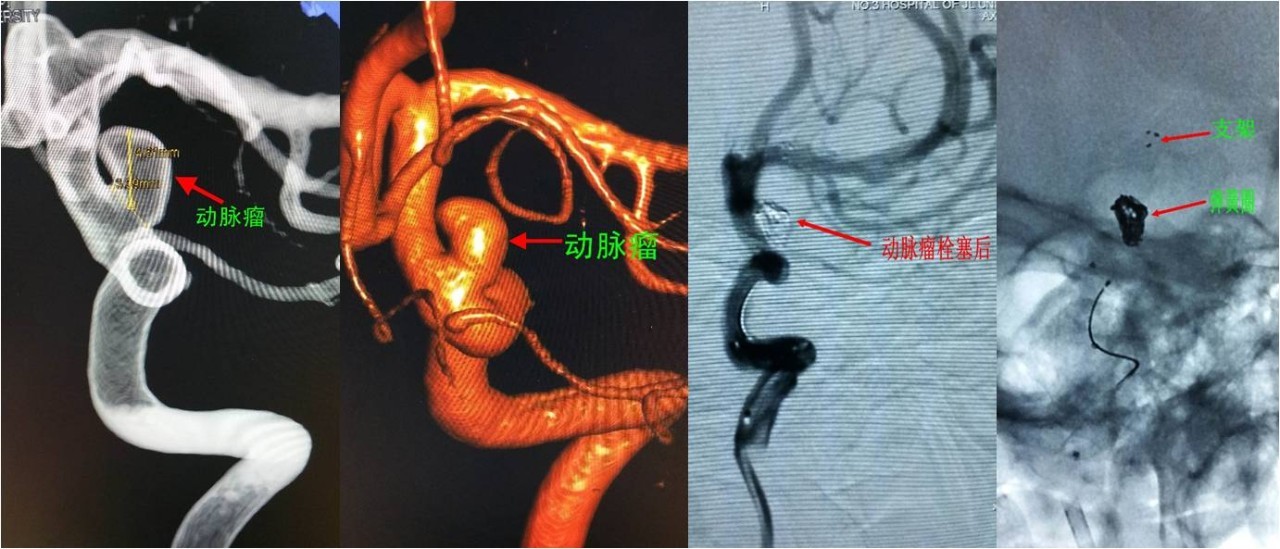

病例3:后交通动脉未破裂动脉瘤栓塞

》女性,23岁,因间断头痛、头晕6个月,加重2天入院,头痛全脑胀痛,不伴有恶心、呕吐,无耳鸣及听力减退,行头颅CT后按“头痛待查”收入我科。

》入院时查体:神经系统查体未见阳性定位体征。